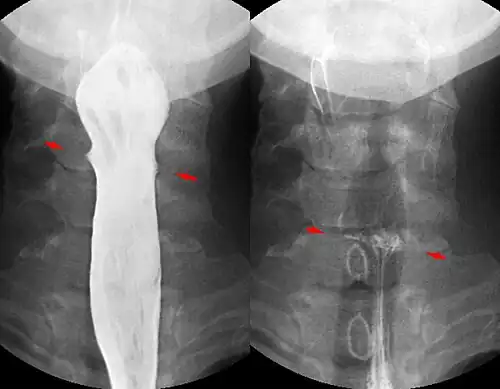

Fish bone pierced in the upper esophagus. Right image without contrast medium, left image during swallowing with contrast medium.

Contrast compounds containing barium or iodine, which are radiopaque, can be ingested in the gastrointestinal tract (barium) or injected in the artery or veins to highlight these vessels. The contrast compounds have high atomic numbered elements in them that (like bone) essentially block the X-rays and hence the once hollow organ or vessel can be more readily seen. In the pursuit of nontoxic contrast materials, many types of high atomic number elements were evaluated. Some elements chosen proved to be harmful – for example, thorium was once used as a contrast medium (Thorotrast) – which turned out to be toxic, causing a very high incidence of cancer decades after use. Modern contrast material has improved and, while there is no way to determine who may have a sensitivity to the contrast, the incidence of serious allergic reactions is low.[1]